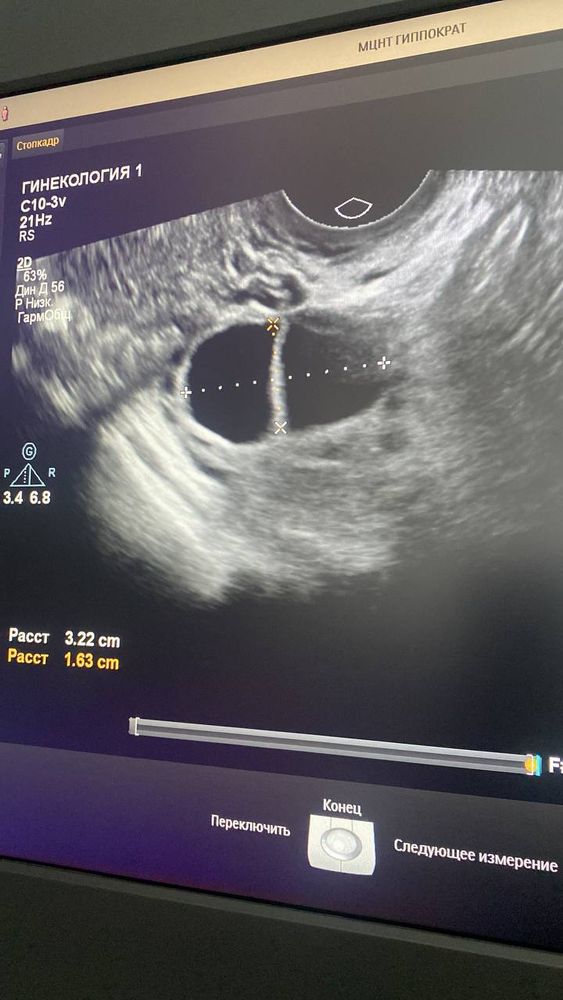

Все таки это были два доминантных фолика. Произошла сегодня овуляция, фух! Читайте прошлые посты*

Вот так меня бестолковый узист вчера довела до паники, что киста уже 35мм и может быть разрыв. Я напугала своего врача (она сейчас в отпуске, удаленно), я накупила вчера на 7.000р свечей по их рекомендациям.

А сегодня утром пошла на узи в другое место и там уже "была овуляция ночью"! Оказалось это 2 дф, один овулировал, второй остался(20мм).

Виктория, у меня не дошло до укола! Перед уколом я пошла на УЗИ и после должна была сразу делать укол, но на узи сказали что это киста, а при кисте нельзя ХГЧ, иначе киста лопнет и всё, хана.

Поэтому без укола, и "с кистой" я ушла домой. Но на утро записалась на УЗИ к другому (толковому) узисту.

Приехала утром и обнаружили что ночью случилась овуляция, сама, без укола ХГЧ.

Узист сказала, что это была не киста с перегородкой, а 2 ДФ рядом. Один совулировал ночью, второй пока 20мм, может тоже будет овуляция еще одна через несколько дней.